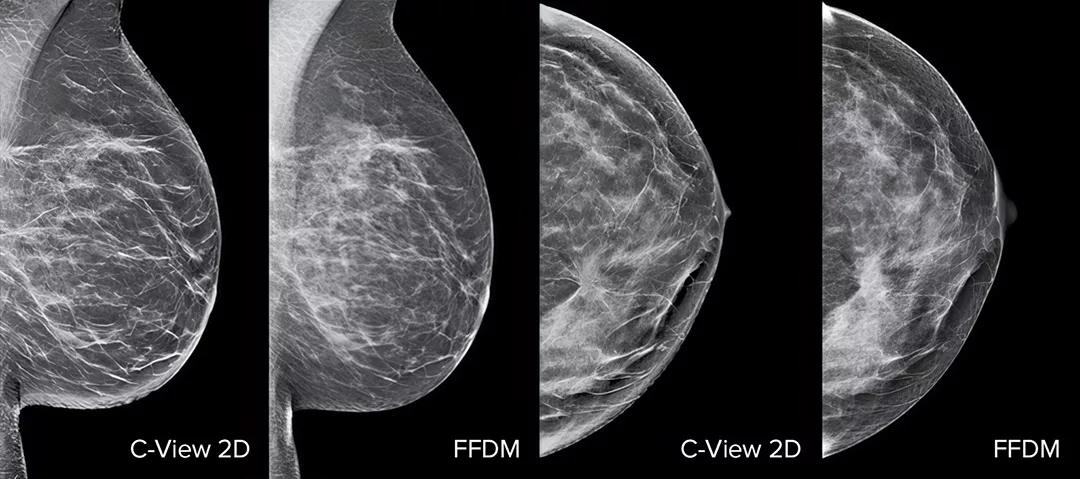

C-View ソフトウェアおよび即座に生成された合成 2D 画像を使用して、乳がん検診のパフォーマンスが向上します1-4。細部が強調され、分析が速くなるだけでなく、患者への放射線量レベルも低減します。C-View 2D 画像は臨床実績があり3,5、トモシンセシス検診検査における FFDM 画像を用いた診断の代替となります。

C-View 2D 画像では、微小石灰化でよく見られる構造の歪み、腫瘤性病変、および輝点が、従来の FFDM 2D 画像や断層スライスよりもよく見えます4,6-9

C-View 2D 画像は臨床実績があり3,5、トモシンセシス検診検査における FFDM 画像を用いた診断の代替としてご使用いただけます。これらの画像は、トモシンセシススライスレビューのナビゲーションの補助にもなります。発表された研究によると、低線量 3D マンモグラフィ検査では、2D 単独の場合と比較して、浸潤がんをより早期に発見し、偽陽性の再検査率も低減することが示されています4,5,7

C-View 2D 画像では、微小石灰化や構築の乱れ、腫瘤性病変、および輝点が、従来の FFDM 2D 画像や断層スライスよりもよく見えます4,6-9